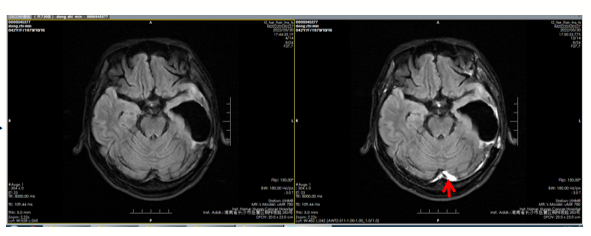

图3 2020年7月脑MR检查结果

2020年7月,全胸CT显示未见明显转移瘤,脑MR显示左侧额叶新发异常信号结节影,考虑脑转移瘤。在系统治疗方案吡咯替尼+卡培他滨的基础上,对脑转移灶进行立体定向放疗(SRT)。最佳疗效为病情稳定(SD),PFS为2+月。